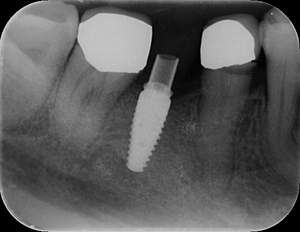

レントゲン写真

- 透過像

| 年齢 | 50代・男性 |

|---|---|

| 主訴 | 右下歯が疼く |

| 治療内容 | ・右下6番インプラント ※1:FGG(遊離歯肉移植術)とは、足りない歯ぐきを上顎から上皮を切り取り移植する外科手術 |

| 治療費 | 合計:902,000円(税込) ■内訳 |

| 治療期間 | 9ヵ月 |

| 治療方針 | 右下の当該歯は歯根破折により保存不可能と診断しました。歯周疾患も伴っていたため抜歯後に骨吸収※1が大きく起こることが予測できました。チタンメッシュ併用骨再生誘導法(GBR※2)を選択しインプラント埋入と同時に行い自然な歯槽骨のラインを再現しました。またGBRを行う際にインプラント辺縁の付着歯肉の減少が起こる為、遊離歯肉移植術(FGG※3)を行い清掃性を考慮した形態に仕上げました。 ■治療方針の解説 治療した右下の歯をレントゲンで撮影したところ根本の部分に黒く写る箇所があり「根尖性慢性周囲炎※1」と診断。また歯周病も進行していました。 ※1 骨吸収・・・歯槽骨という歯を支える骨がなくなっていくこと |

| 担当者所見 | 主訴の右下だけでなく歯茎の腫れ、発赤があり不良補綴や不良充填など他にも治療箇所が多数ありました。プラークコントロールが不良であった為まずはブラッシング指導を行いセルフケアの重要性を理解していただくところからスタートしました。 右下6番の歯はインプラント治療を行なった結果審美的にも機能的にも患者様の満足を得ることができました。骨造成と歯肉移植も行なった為インプラントを支える十分な歯周組織の獲得ができたと思っております。 |